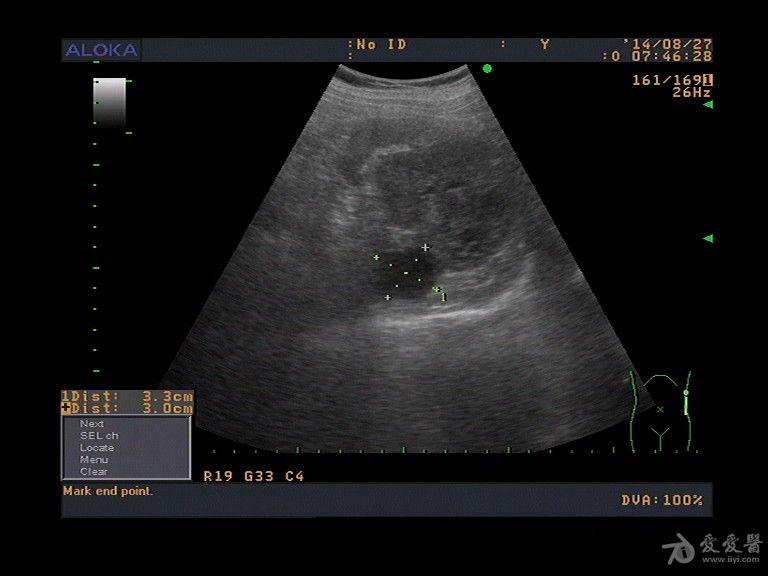

肾肿瘤彩超

肾肿瘤彩超,肾肿瘤ct

肾肿瘤超声鉴别诊断

肾结核?肾肿瘤?

体检时超声要尽量防止漏诊肾癌